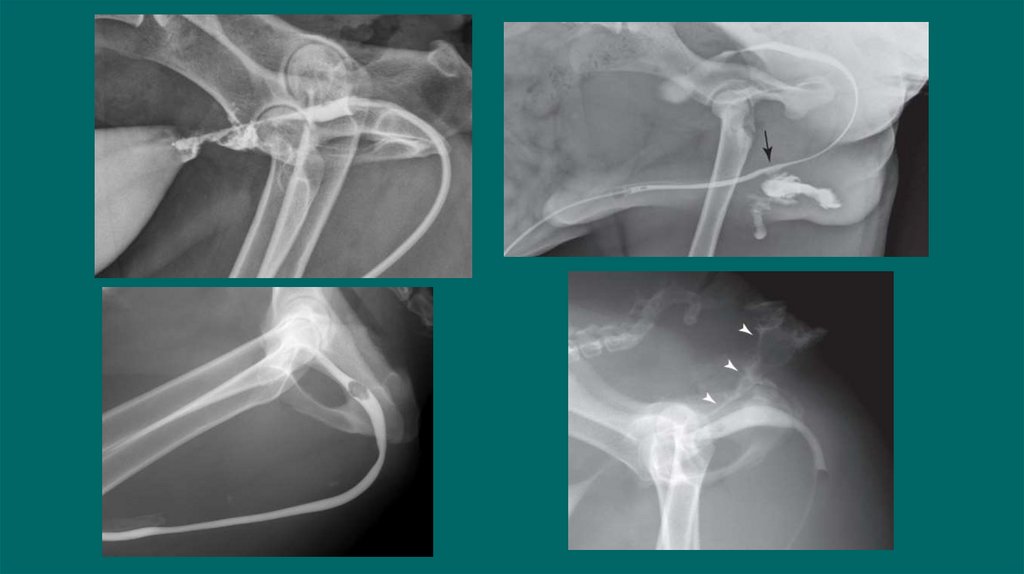

40. Экскреторная урография

Рентгенологическое исследование с внутривенным введением контраста .

Показания:

Субъективно функцию почек СКФ, пиелоэктазию, гидронефроз, оценить проходимость

мочеточников, обнаружение эктопии мочеточников ,обнаружении разрывов на уровне от

мочеточников до мочевого пузыря

Подготовка пациента:

1.Голодная диета 12-24 ч, при необходимости очистительная клизма.

2.Стабильная гемодинамика

3.Установка в/в катетера/Инфузия

4.При необходимости под седацией

Техника

Получение обзорных боковых и ВД снимков (важно отсутствия каловых масс

Введение йодсодержащего контраста в дозе 400-800мг/кг йода(Омнипак,Урографин) в/в болюсно

Получаем латеральные и ВД снимки сразу после введения контраста ,а затем через 5,20, и 40 минут

Для обнаружения эктопии мочеточника могут быть использованы косые снимки

Рекомендован в/в ведение жидкостей в момент или после для поддержания гидратации и индукции диуреза.

42. Пиелография

Определения локализации обструкции мочеточников у кошек с азотемией

Снижен риск попадания контраста в почки при нефропатии

Проводится под УЗИ контролем.

Тонкоигольная аспирация содержимого из лоханки(пиелоцентез)

Спинальной иглой или иглой диаметром 22G вводят под углом 45

Введение йодсодержащего контраста йода(Омнипак,Урографин)

Объем контрастного вещества должен составлять половину объема аспирационной мочи

Dominique Penninck, Marc-Andre d Anjou.2008-2015